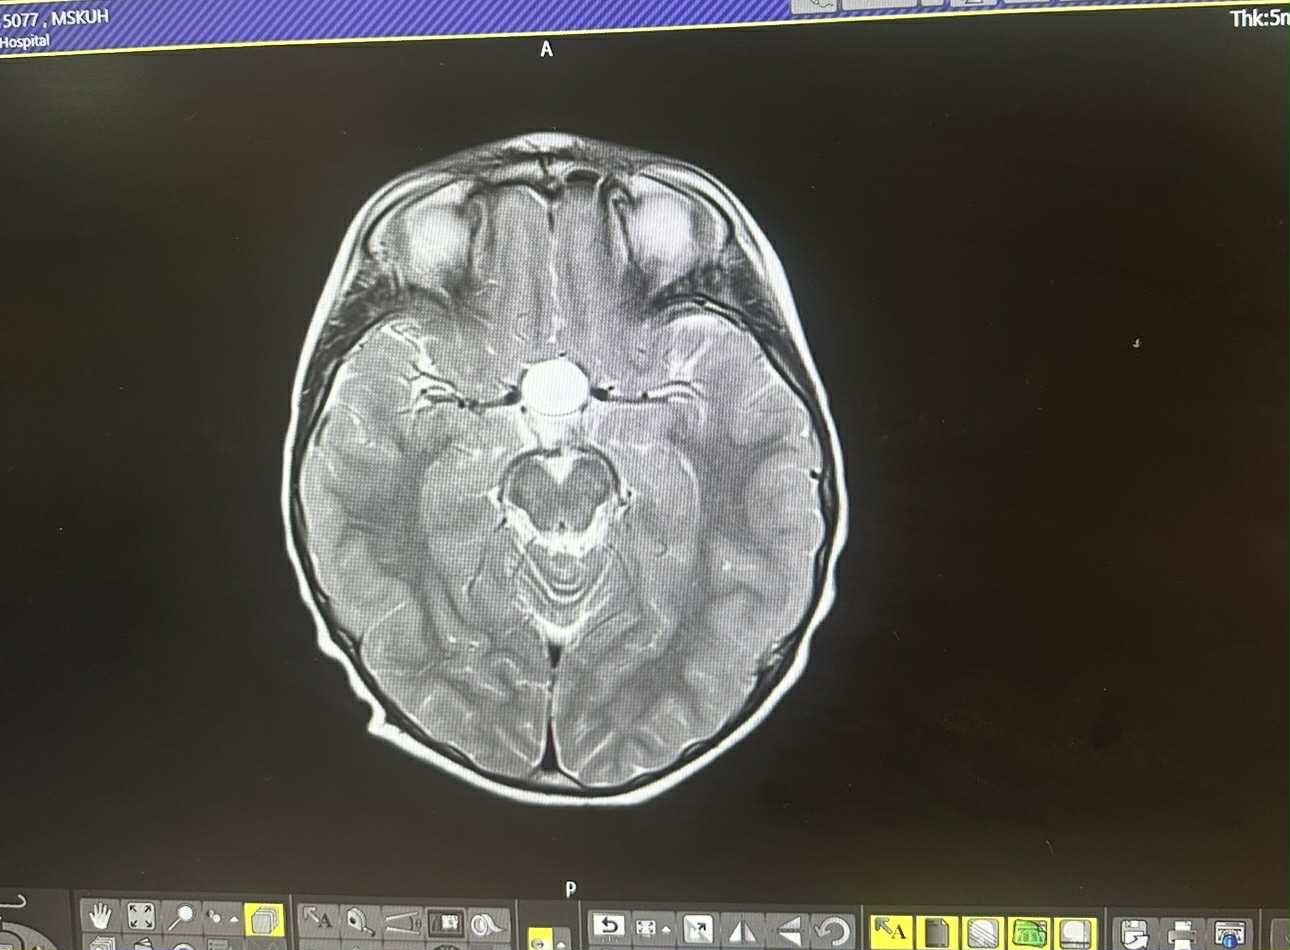

Marley has been diagnosed with crangiopharyngioma, a rare slow growing tumour that has developed just above the pituitary gland in his brain. Marley is facing brain surgery and radiotherapy and a gruelling lifelong journey ahead of him.